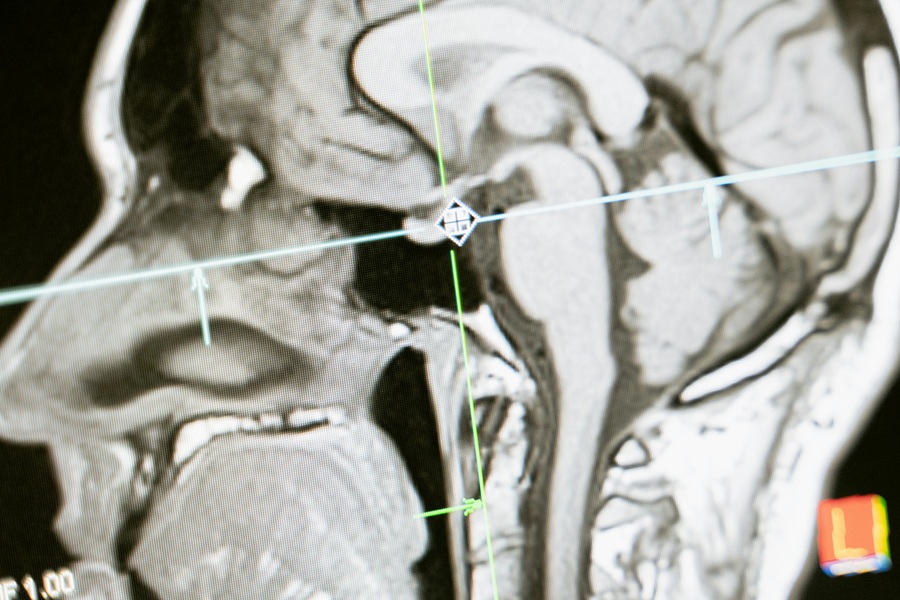

Οι συμμετέχοντες υποβλήθηκαν σε γνωστικά τεστ πριν και μετά το πρόγραμμα, καθώς και τρεις μήνες αργότερα. Η ακετυλοχολίνη μετρήθηκε μέσω τομογραφιών PET. Σύμφωνα με τις τομογραφίες, η ομάδα παρέμβασης παρουσίασε αύξηση 2,3% στη ρύθμιση της ακετυλοχολίνης μετά το δεκάβδομο πρόγραμμα ταχείας εκπαίδευσης. Η βελτίωση σημειώθηκε σε περιοχές του εγκεφάλου που σχετίζονται με τη μνήμη και τη λήψη αποφάσεων.